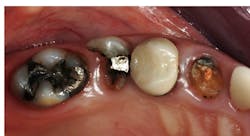

My suggestions are based on the dental literature and my many years of practice experience. Consider the factors below to help you decide whether pins or posts are needed. Figures 1–3 show the need for the restorative buildup procedures.

Previous caries experience

This problem is easily judged visually by observing previous restorations or current caries and varies markedly among patients requiring tooth buildups. Resin-based composite is the most common buildup material, but it is not cariostatic. Conventional glass ionomers (Fuji I or Ketac Cem) or resin-modified glass ionomers (Fuji 2 LC or Ketac Cem) should be considered as buildup materials for patients with high caries activity who do not have aggressive occlusion. Because their strength is lower than composite resin, they are best suited for single-crown buildups only—not as abutments.